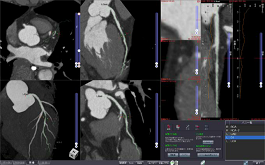

CT CORONARY ANALYSIS

With contrasted CT images, this protocol automatically extracts the coronary arteries and displays the results in views such as MIP, CPR, and Straight CPR. Calculation of vessel stenosis is available.